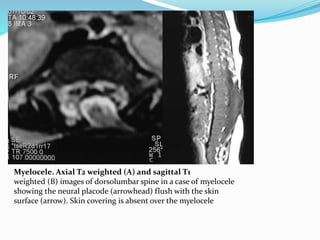

Myelocele. Axial T2 weighted (A) and sagittal T1

weighted (B) images of dorsolumbar spine in a case of myelocele

showing the neural placode (arrowhead) flush with the skin

surface (arrow). Skin covering is absent over the myelocele